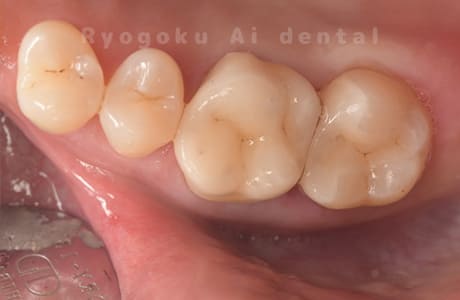

-

- 原因

- 重度カリエス

- 治療内容

- 抜髄治療、マイクロエンド

- 治療費用

- 99,000円

- 担当医

- Dr. 炭野

虫歯が大きく、神経の保存ができなかったため、マイクロエンド治療を行いました。